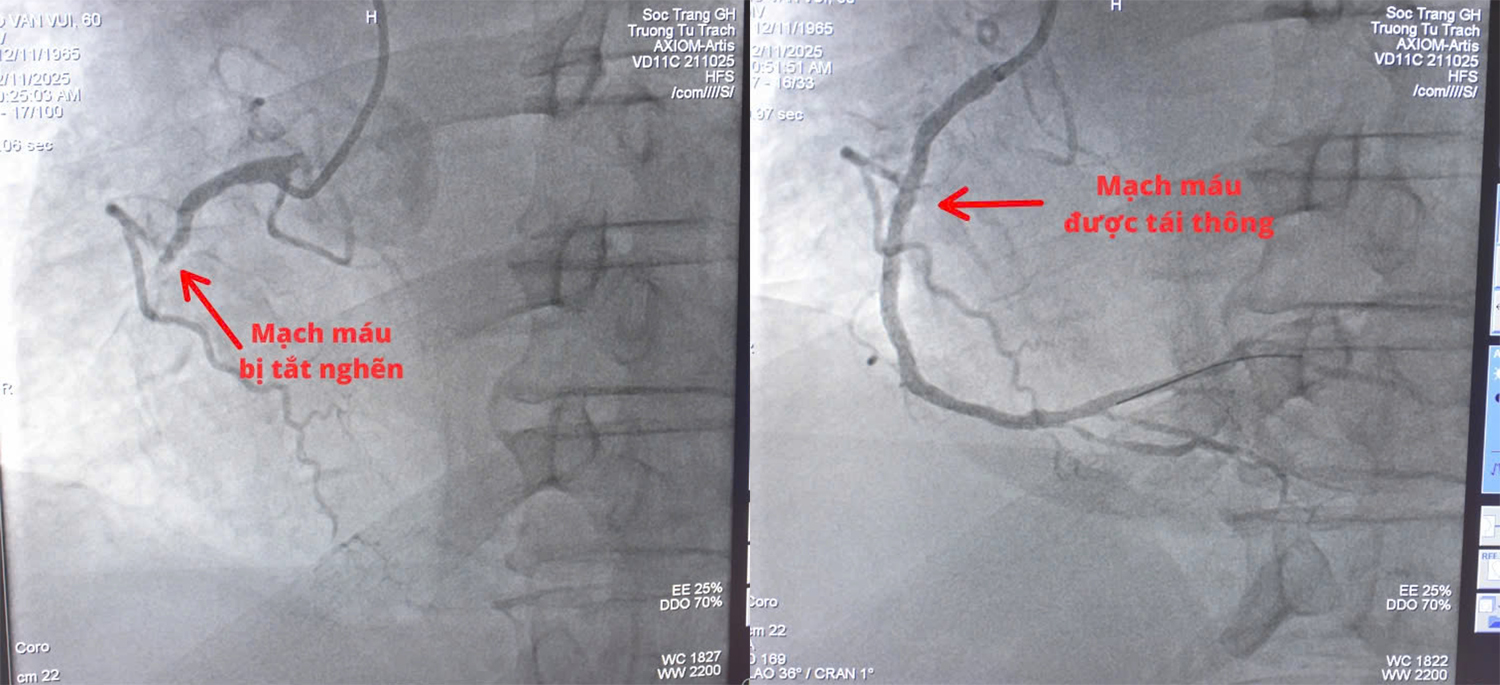

Kết quả chụp mạch vành ghi nhận bệnh nhân có một nhánh động mạch vành bị tắc nghẽn nên đặt một stent để khai thông vị trí hẹp. Hiện, sức khỏe bệnh nhân ổn định, dự kiến có thể xuất viện vào đầu tuần sau.

Hình ảnh trước và sau khi đặt stent để khai thông vị trí hẹp.